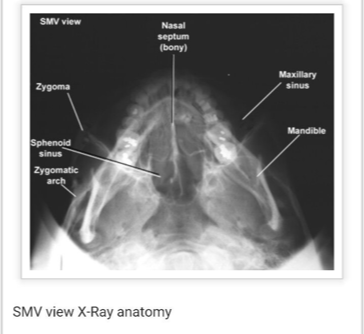

Submentovertical of the cranial base - Schuller method

Submentovertical of cranial base - Schuller method